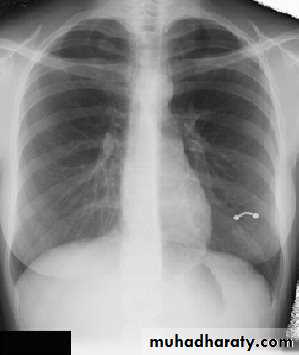

• Alveoiar oedema (‘Bat’s wings’)

• Kerlev B lines (interstitial oedema)

• Prominent upper lobe vessels

• Cardiomegaiy

• Pleura

• effusion